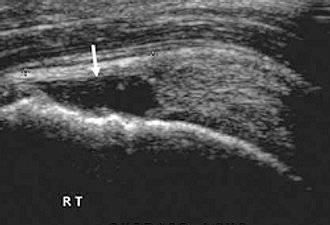

SHOULDER Supraspinatus tendon Ultrasound images were collected using a 4–12-MHz linear transducer in B-mode of the supraspinatus tendon in the transverse (short axis) and the anterior aspect of the subacromial space outlet. Using image callipers, measurements of tendon thickness were ... Content Retrieval